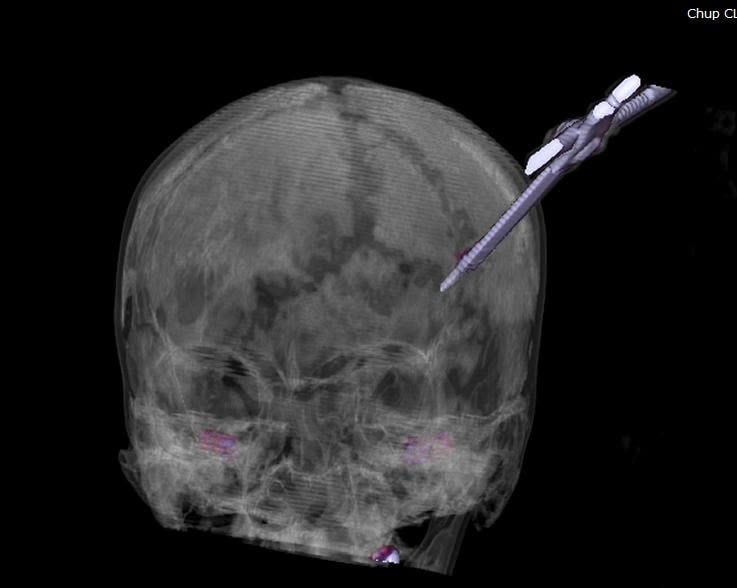

Nhận định đây là ca chấn thương sọ não phức tạp, lập tức người bệnh được chụp cắt lớp vi tính sọ não để đánh giá chính xác vị trí tổn thương và mức độ đâm xuyên của dị vật. Từ đó có đường mổ an toàn, hạn chế tối đa tổn thương não, tránh biến chứng nặng.

Dưới sự chỉ đạo trực tiếp của BSCKII Nguyễn Tiến Dũng - Phó Giám đốc Bệnh viện, kíp mổ hội chẩn với các chuyên khoa, đánh giá đây là vết thương xuyên sọ sâu khoảng 5cm xâm lấn nhu mô não, nguy cơ chảy máu sâu bên trong não kèm nguy cơ nhiễm trùng lan rộng do dị vật găm xuyên sọ. Do đó, bệnh nhân lập tức được chuyển phòng mổ cấp cứu lấy dị vật, xử trí tổn thương não.